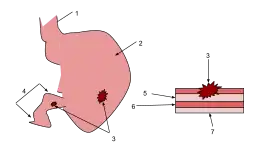

- Esophagus

- Stomach

- Ulcers

- Duodenum

- Mucosa

- Submucosa

- Muscle

Peptic ulcers are a form of acid–peptic disorder. Peptic ulcers can be classified according to their location and other factors.

Microscopic appearance

A gastric peptic ulcer is a mucosal perforation that penetrates the muscularis mucosae and lamina propria, usually produced by acid-pepsin aggression. Ulcer margins are perpendicular and present chronic gastritis. During the active phase, the base of the ulcer shows four zones: fibrinoid necrosis, inflammatory exudate, granulation tissue and fibrous tissue. The fibrous base of the ulcer may contain vessels with thickened wall or with thrombosis.[35]